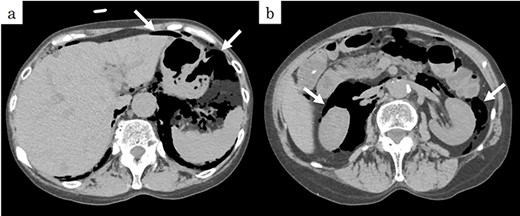

On chest and abdominal CT, free gas was observed in the entire abdominal cavity (Fig. 1a), and extensive emphysema was also observed in the retroperitoneum (Fig. 1b). In addition, it was observed from the mediastinum to both sides of the necks (Fig. 2).

Preoperative CT showed (a) pneumoperitoneum (arrows) and (b) a massive pneumoretroperitoneum (arrows).